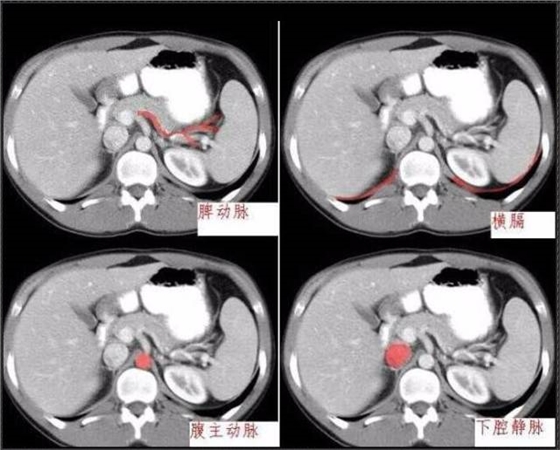

秒懂:腹部 CT 看這篇就夠